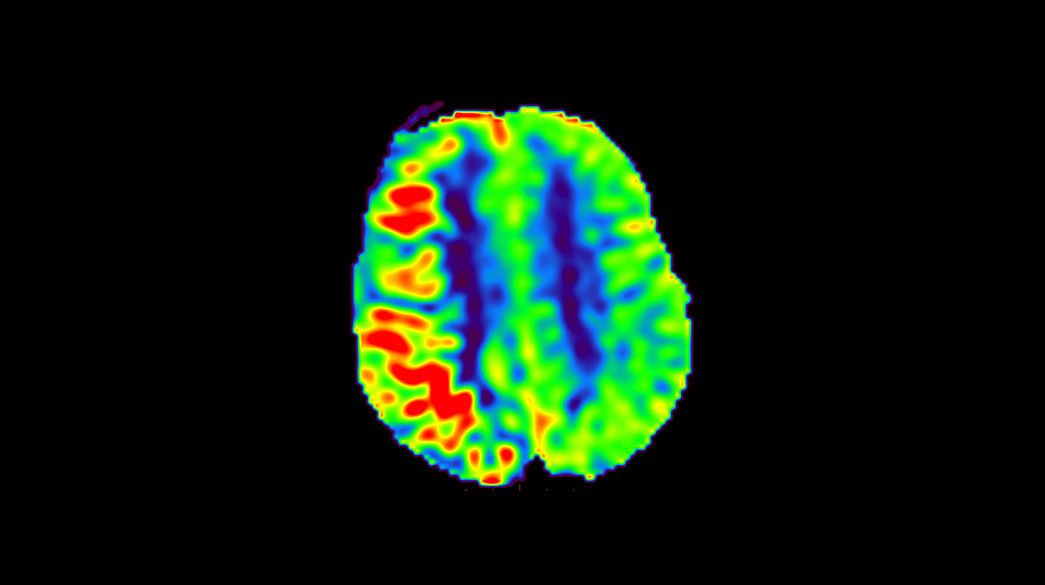

3D-Arterial-Spin-Labeling1040-x-585

Read case study